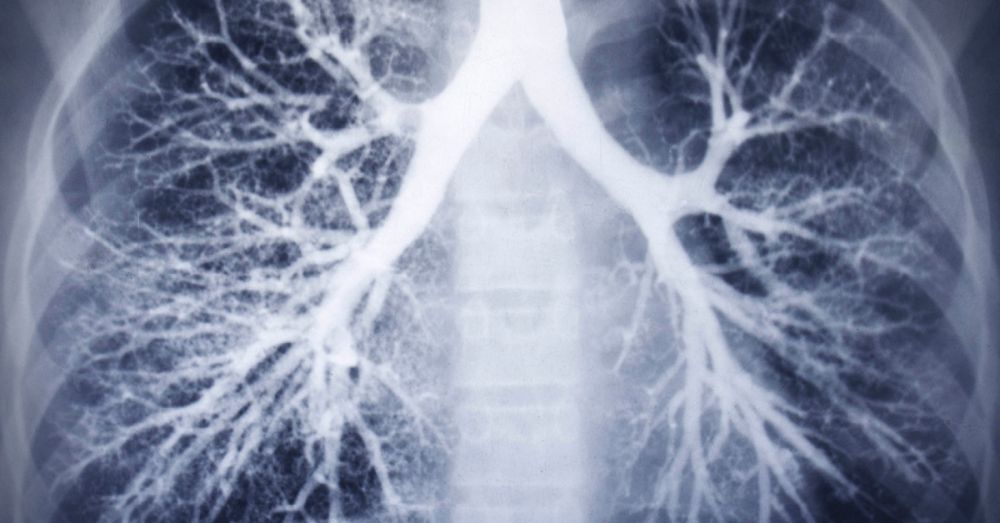

„Pacienty, kteří prodělali covid-19, pošle pneumolog vždy na rentgen plic, provede tzv. spirometrii – tedy funkční vyšetření plic včetně difuze, změří nasycení krve kyslíkem jak v klidu, tak po zátěži,“ popisuje prim.

MUDr. Ivana Čierna Peterová, předsedkyně Sekce ambulantních pneumologů. Jak dále uvádí, v její plicní ambulanci v Brandýse nad Labem je z nově příchozích přibližně třetina „postcovidových“. Podobně je tomu i v pražském plicním zařízení Medicon.

„Je nás zde osm lékařek a každý týden vyšetříme asi 40 nově příchozích postcovidových pacientů. Naštěstí jsme zatím téměř u nikoho neshledali závažné poškození plic, a to ani u těch, kteří byli na ventilátoru.

Jen u nízkého procenta se objevují jisté patologie – mají například sníženou plicní difuzi či ventilační poruchu a v takových případech řešíme, zda léčit nebo sledovat, jestli se porucha sama časem nezlepší,“ říká doc. MUDr. Václava Bártů, Ph.D. z Medicon.

Nejčastěji u nich vidíme poruchy plicní difuze a poruchu okysličení krve zejména při zátěži. Zajímavé je, že se vyskytují i lidé, u nichž se na CT plic objeví fibrotické změny, a oni nepociťují, že by se jim hůře dýchalo.